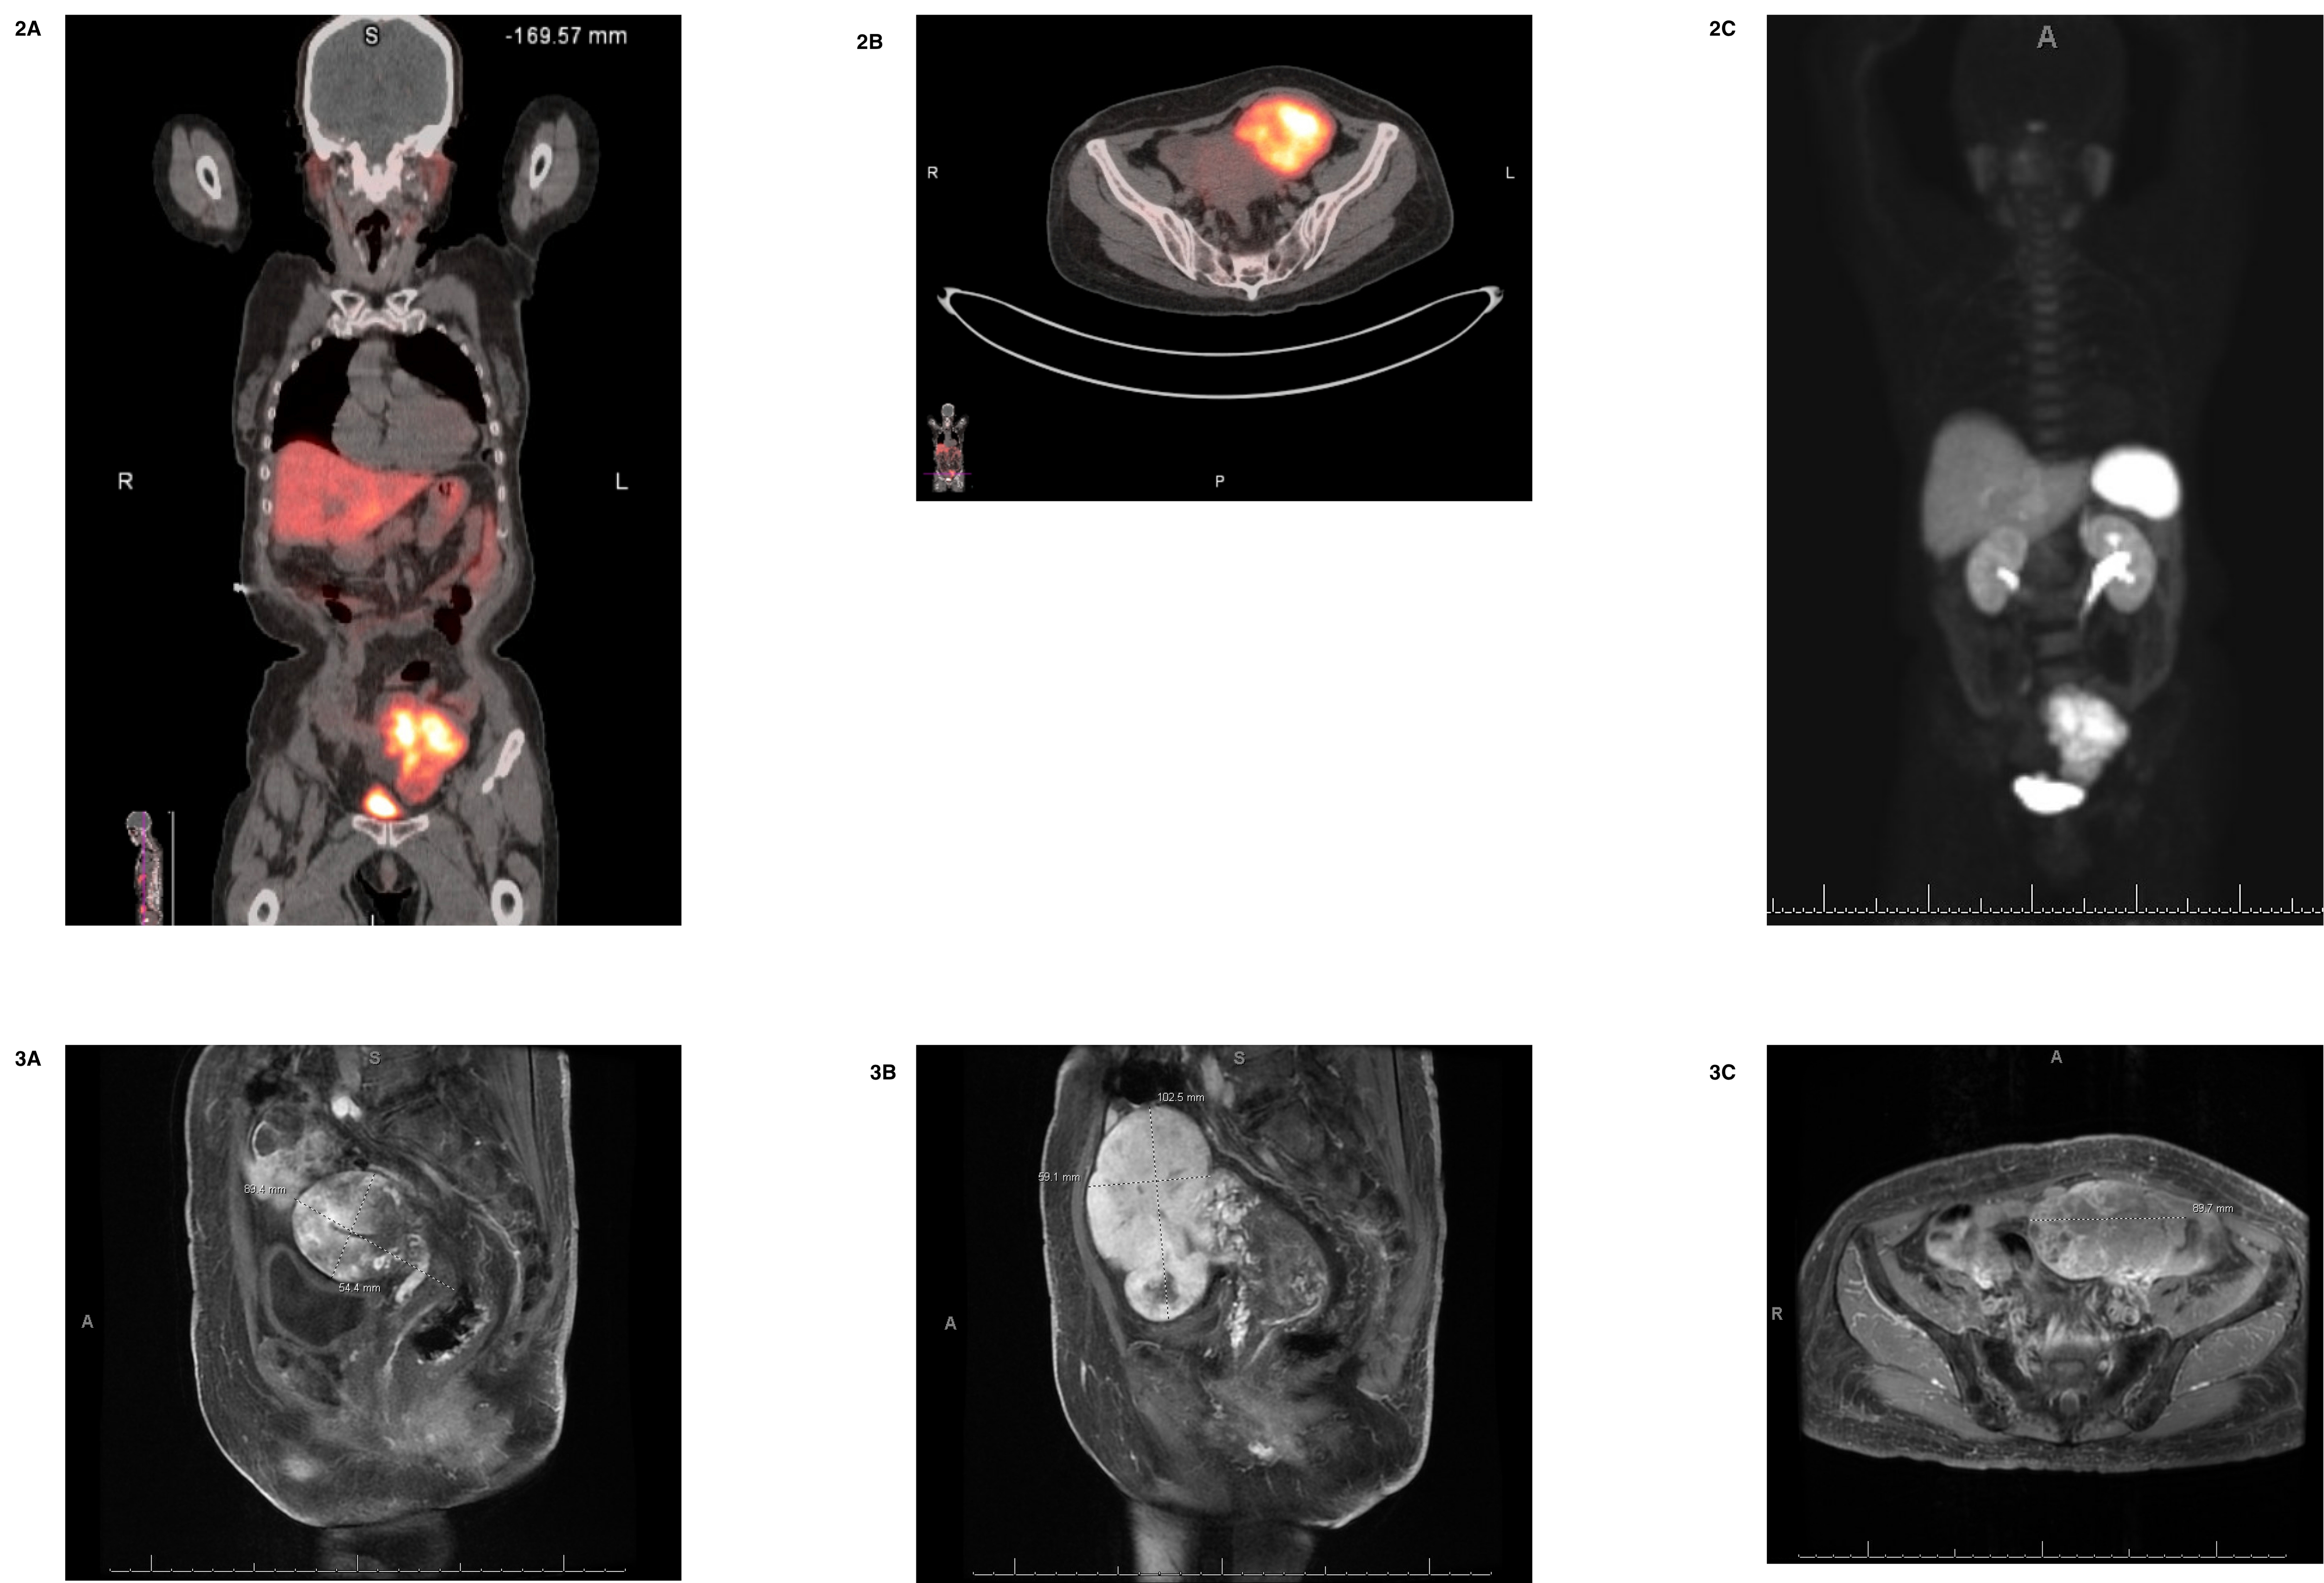

Given the flushing and TEE findings, CHD was suspected. A 24-hour urine 5-HIAA was markedly elevated at 81 mg, confirming carcinoid syndrome. Right heart catheterization revealed elevated RH pressures, torrential TR, and normal cardiac index. PET-CT showed a large pelvic mass arising from the left ovary with Ga-68 DOTATATE uptake in mediastinal and hilar nodes, consistent with metastatic disease (Fig 2). Pelvic MRI confirmed the ovarian mass concerning for NET (Fig 3). She was started on octreotide LAR 20 mg every 4 weeks by Medical Oncology, evaluated by cardiothoracic surgery, and underwent surgical replacement of the aortic, tricuspid, and pulmonic valves. Her postoperative course was complicated by pneumomediastinum and upper GI bleeding due to a Mallory-Weiss tear.

CHD is a serious manifestation of carcinoid syndrome, caused by serotonin-induced fibrous plaque deposition on tricuspid and pulmonic valves, leading to immobile leaflets and severe regurgitation. Primary ovarian NETs causing CHD are exceedingly rare, with only isolated case reports. Clinicians should suspect CHD in patients with right-sided heart failure, flushing, or characteristic echocardiographic findings—such as thickened valves and hepatic vein flow reversal—and confirm with elevated 5-HIAA levels.